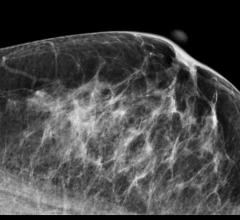

Despite decades of progress in breast imaging, one challenge continues to test even the most skilled radiologists ...

The American College of Radiology (ACR) and the Society of Breast Imaging (SBI) are encouraging congressional leaders to pass the Protecting Access to Lifesavings Screenings Act (H.R. 3339). Passage of the act would ensure women who want to get regular mammograms retain insurance coverage with no copay and avert thousands of unnecessary deaths.